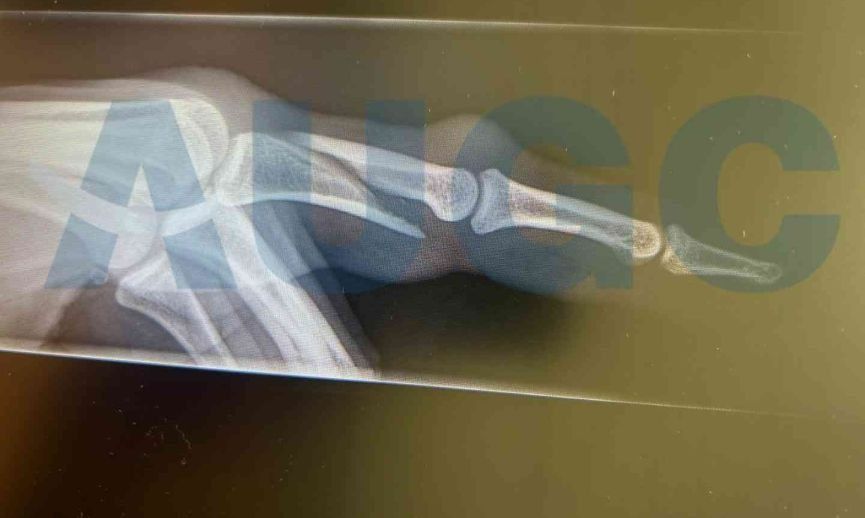

Imagen de la radiografía de la fractura del agente de la Guardia Civil. AUGC

El pasado viernes, varios agentes que prestaban servicio en el aeropuerto de Lanzarote, recibieron un aviso de que había varios pasajeros habían tenido una reyerta durante un vuelo procedente de Edimburgo. Según la tripulación del vuelo, estos se encontraban bajo los efectos de alguna sustancia. Los guardias civiles, intentaron tranquilizar a un individuo de unos 36 años de edad quien mostraba una actitud hostil, pero no pudieron evitar que este les propinara patadas y puñetazos, causando a uno de ellos la fractura de uno de los dedos de la mano.